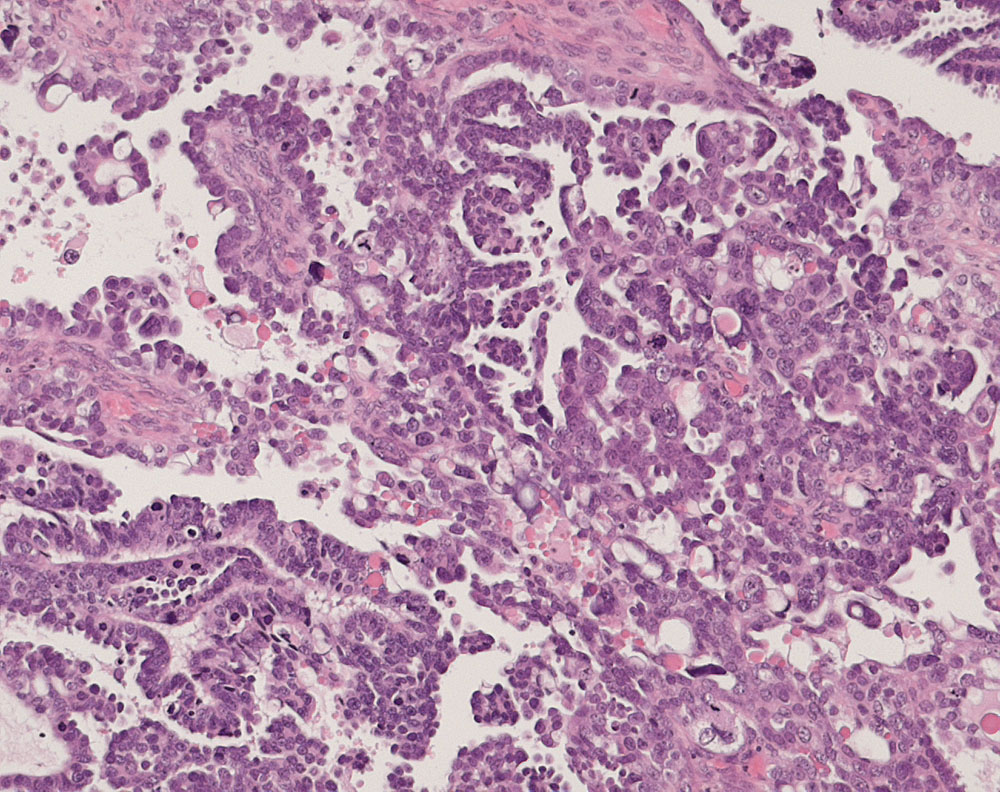

PathoPic ID 10934 - seröses Ovarialkarzinom high grade

seröses Ovarialkarzinom high grade

maligner Tumor

Ovar

Genitalorgane, weiblich

Papillärer Tumor bestehend aus stark atypischen und vereinzelt bizarren pleomorphen Tumorzellen mit starken Kerngrössenschwankungen. Mehrere, teils

atypische Mitosen und Apoptosen.

Verdacht auf Ovarialkarzinom (CA125 > 2000u/l). CT: Vergrösserte Ovarian beidseits. Maligner Pleuraerguss Adenokarzinom.

Histologie

100

58